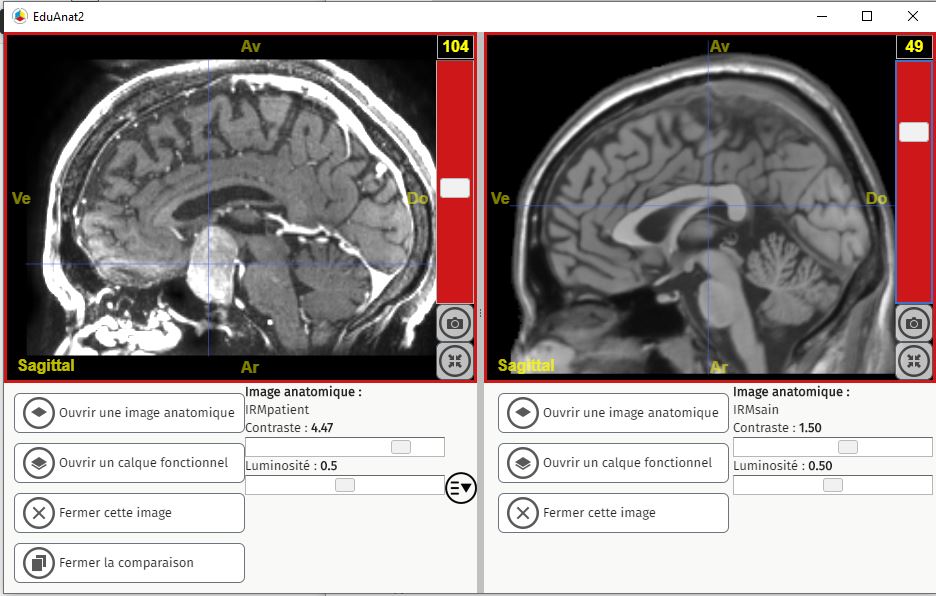

En ouvrant l’IRM avec EduAnat2, l’élève obtient ceci :

Comme on peut le constater, une tumeur est nettement visible au niveau de l’hypophyse.

L’exploitation des 2 IRM permet à l’élève de confirmer cette hypothèse. L’IRM abdominale étant normale, on écarte définitivement l’hypothèse d’une anomalie des surrénales. Par contre, en comparant avec EduAnat2 l’IRM d’un individu sain à celui du patient, l’élève identifiera immédiatement une masse claire de grande taille au niveau de l’hypophyse.

L’élève conclura que l’hypophyse du patient présente une anomalie (visible sous la forme d’une masse claire, il n’est pas attendu qu’il parle de tumeur) certainement à l’origine d’une forte sécrétion d’ACTH et donc de cortisol. C’est cette cortisolémie très élevée qui est à l’origine des maux du patient (rétention d’eau, glycémie élevée et indirectement obésité).